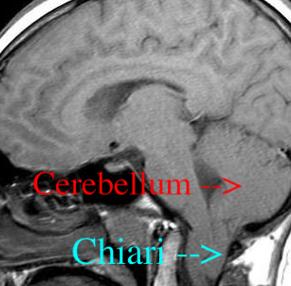

MRI normal brain -   At 6 o'clock on the image, round topped vertical white bone (dens-C2)         is below a large white almost triangular pointy bone (clivus). Brain stem (grey oval) is behind strip of black (spinal fluid - CSF). Brain stem controls everything that keeps you alive.

Cerebellar tonsil is the olive shaped grey tissue directly behind the spinal cord at the base of the occiput.

Example of Arnold Chiari (ACM) - back of brain (cerebellar tonsils) hanging down through foramen magnum (where the spinal cord enters the skull) taking up room that the spinal cord should have.

THIS IMAGE IS NOT ME